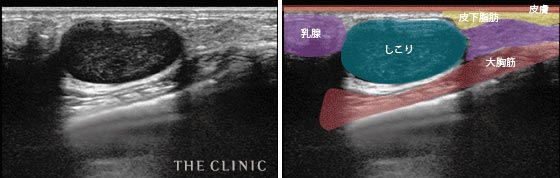

- しこりの大きさ

- 大きなしこりとして残ってしまった症例